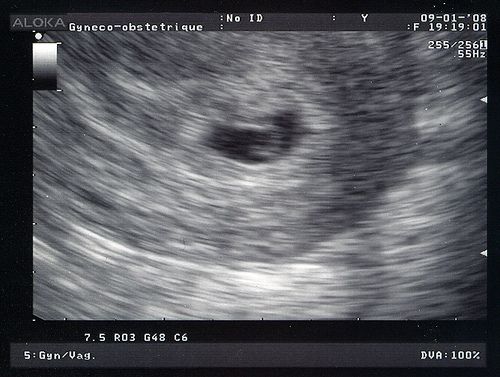

Tu as déjà bien grandi! Le sac est passé de 4 à 14 mm en une semaine. Toi, tu mesures maintenant 2 mm!

Je ne regrette pas d'avoir été te voir, même si c'était à cause de ce foutu stress! Tu ressembles à une virgule un peu plus claire dans le sac foncé.